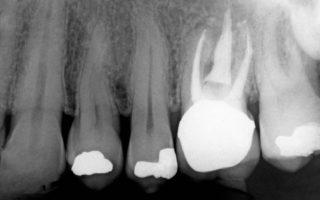

Leczenie kanałowe pozwala na uratowanie zębów, które w przeciwnym razie trzeba by wyrwać